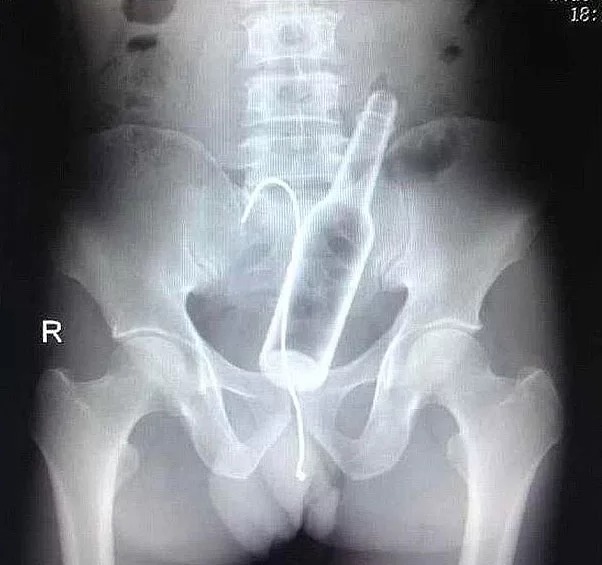

O Şişe Oraya Nasıl Girmiş Bakın!

Röntgen filmlerinden çıkan akıl almaz görüntüler: